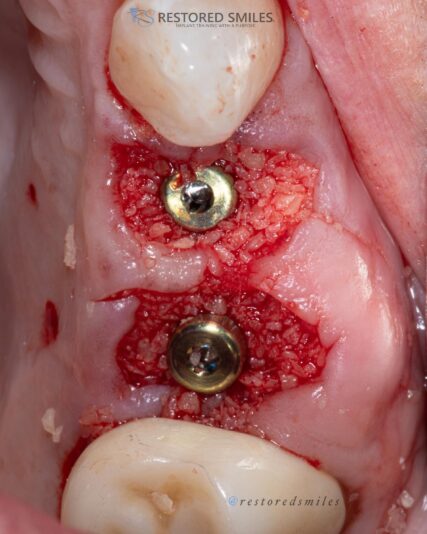

There was two failing anterior incisors with significant infection that had to be removed and we placed two immediate implants into sites with severe bony defects. We performed simultaneously GBR/GTR using CGF/PRF protocols. After 6 months of healing we fortunately had a great outcome with ample bone.

There’s always a nervous excitement when…